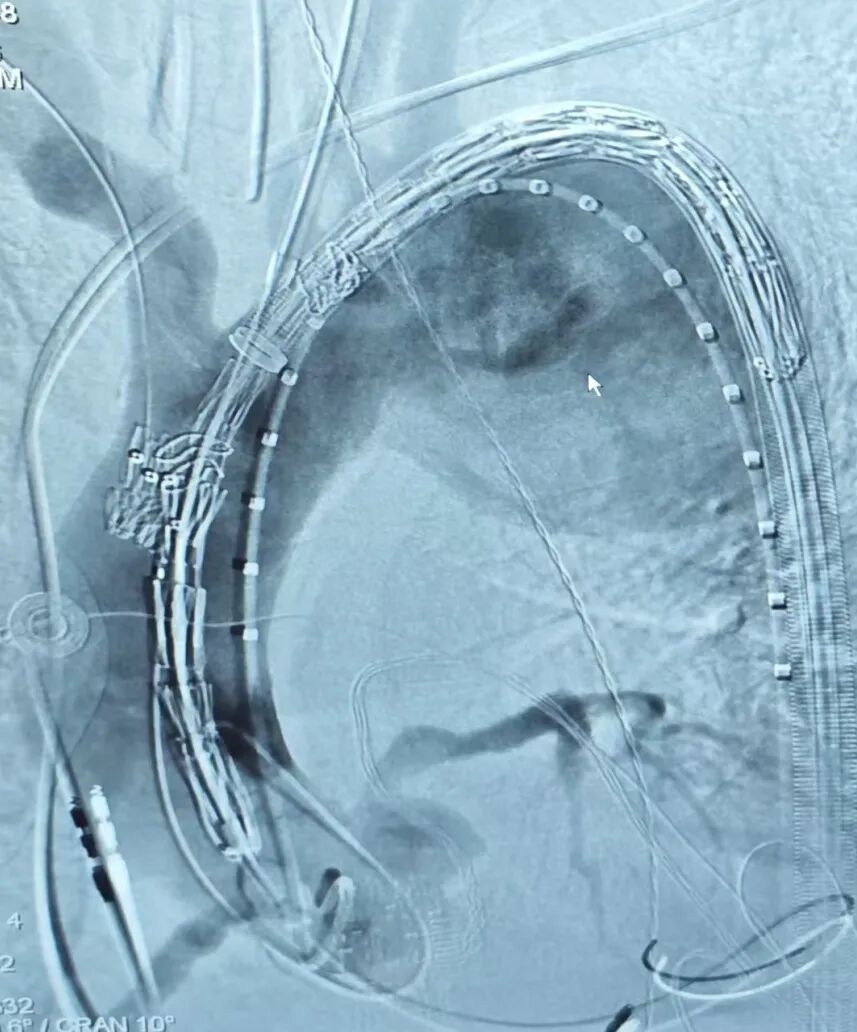

新加坡病例分享

新加坡病例手术在陈笃生医院(Tan Tock Seng Hospital)由Glenn Tan教授及其团队实施。该患者诊断为主动脉弓动脉瘤,瘤体累及左锁骨下动脉,直径达6.7cm,常规腔内手术均无法安全重建全部分支血供。患者血管解剖结构复杂,左椎动脉迷走,腔内治疗需同时完成弓上四分支的重建,这使得治疗难度进一步增加。医生团队在与心脉医疗?团队充分沟通后,决定采用定制化四分支Hector?/通天戟?胸主多分支支架进行治疗。通过单次腔内介入,精准通过其一体式分支支架重建了无名动脉、内嵌通道重建左颈总动脉,通过预埋导管重建迷走左锥动脉和导丝超选重建左锁骨下动脉,完成了全球首例四分支Hector?/通天戟?胸主多分支支架植入手术。手术过程顺利,术中无并发症,术后血管造影结果优异,瘤体被有效隔绝。

▲术中造影

▲术后造影